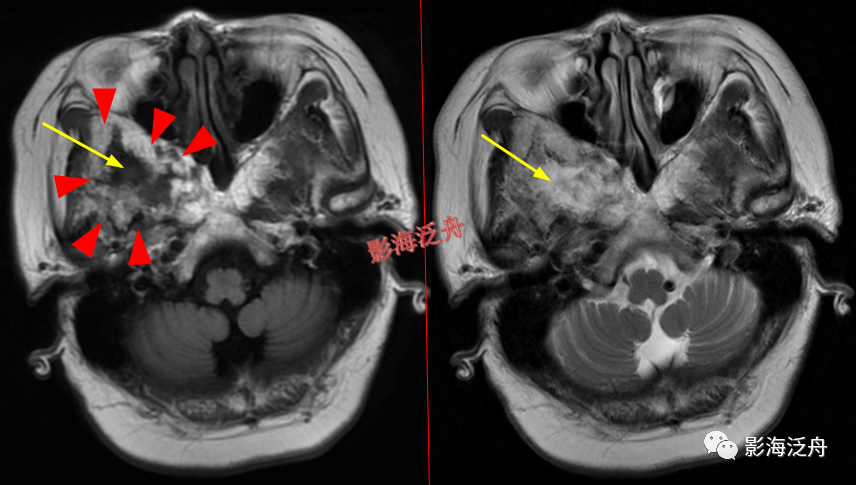

左侧岩尖部囊性病变(红箭头),患者未术,病理不明。MR对骨质结构显示不佳,因此很多读者会忽略掉颅内骨质病变的观察,很多颅内病变,如三叉神经鞘瘤、鼻咽癌等都会造成颞骨岩部(红色标注区)骨质破坏,因此,平时应对此处多加留意。黄箭头指听神经及内耳结构。

蝶骨骨纤维异常增殖症(红箭头),病灶内部可见特征性的囊变区(黄箭)。蝶骨的病变在MR上识别起来更为困难,因为蝶骨位于颅底部,此处骨骼、肌肉、脂肪等多种组织成分混杂,导致正常情况下也看起来非常乱。不要着急,慢慢学。